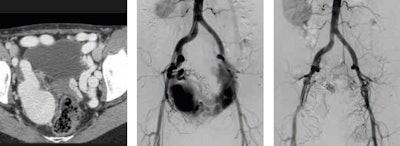

He thinks retroperitoneal hematoma adjacent to an abdominal aortic aneurysm is the most common imaging finding indicative of aneurysm rupture. Endovascular aneurysm repair (EVAR) has become an established technique for the treatment of many infrarenal aortic aneurysms. Less invasive than open surgical repair, EVAR is associated with better outcomes, according to Pyra (see figures 1 and 2).